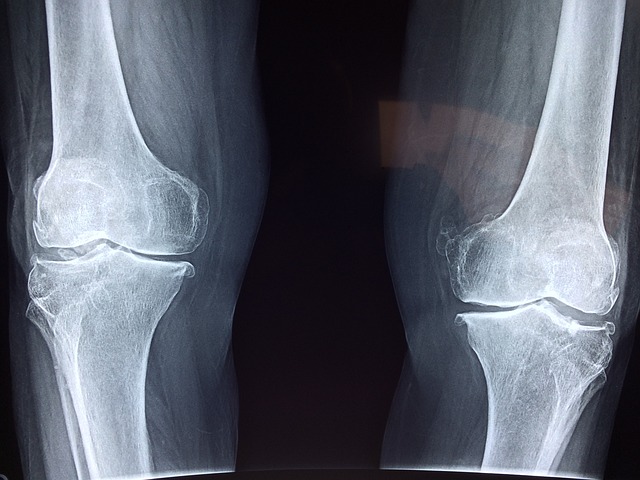

겨울철에는 기온이 낮아지면서 관절 통증이 심해지는 경우가 많습니다. 특히 관절염 환자나 노년층의 경우 추운 날씨가 관절 건강에 부정적인 영향을 미칠 수 있어 적절한 관리가 필요합니다. 관절 건강을 유지하려면 온열 요법을 활용해 관절을 따뜻하게 하고, 꾸준한 스트레칭으로 유연성을 유지하며, 영양소를 적절히 섭취하는 것이 중요합니다. 이번 글에서는 겨울철 관절 건강을 지키기 위한 효과적인 관리법을 소개합니다.

겨울철에는 낮은 기온과 건조한 환경이 관절 통증을 악화시키는 원인이 됩니다. 특히 기온이 내려가면 관절 주변의 근육과 인대가 경직되면서 움직임이 둔해지고, 이로 인해 통증이 심해질 수 있습니다. 따라서 관절을 따뜻하게 유지하는 것이 매우 중요합니다. 온열 요법은 혈액순환을 촉진하고 근육을 이완시켜 관절 건강을 개선하는 데 효과적인 방법입니다. 온열 요법의 가장 간단한 방법은 따뜻한 찜질을 활용하는 것입니다. 온찜질은 관절 주위의 근육을 부드럽게 하고 혈류를 증가시켜 관절의 유연성을 높여줍니다. 온찜질을 할 때는 찜질팩을 사용하거나 따뜻한 물수건을 관절 부위에 올려두는 것이 좋습니다. 찜질팩은 15~20분 정도 사용하면 충분하며, 너무 뜨거운 온도는 피부에 손상을 줄 수 있으므로 주의해야 합니다. 또한, 따뜻한 물에 몸을 담그는 반신욕도 관절 건강에 도움을 줍니다. 반신욕을 하면 전신의 혈액순환이 활발해지고, 관절과 근육이 이완되면서 통증이 줄어드는 효과가 있습니다. 물의 온도는 38~40도 정도가 적당하며, 15~20분 정도 유지하는 것이 좋습니다. 여기에 에센셜 오일이나 허브를 첨가하면 근육 이완 효과를 더욱 높일 수 있습니다. 일상생활에서 관절을 따뜻하게 유지하는 것도 중요합니다. 특히 외출할 때는 보온성이 좋은 의류를 착용하고, 관절 부위를 보호할 수 있는 무릎 보호대나 손목 보호대를 활용하는 것이 좋습니다. 또한, 실내에서도 체온을 유지할 수 있도록 발열 내의나 두꺼운 양말을 신는 것이 도움이 됩니다. 겨울철 난방을 적절히 유지하여 실내 온도를 20~22도 사이로 맞추고, 습도를 40~60% 정도로 조절하면 관절 건강을 유지하는 데 유리합니다.